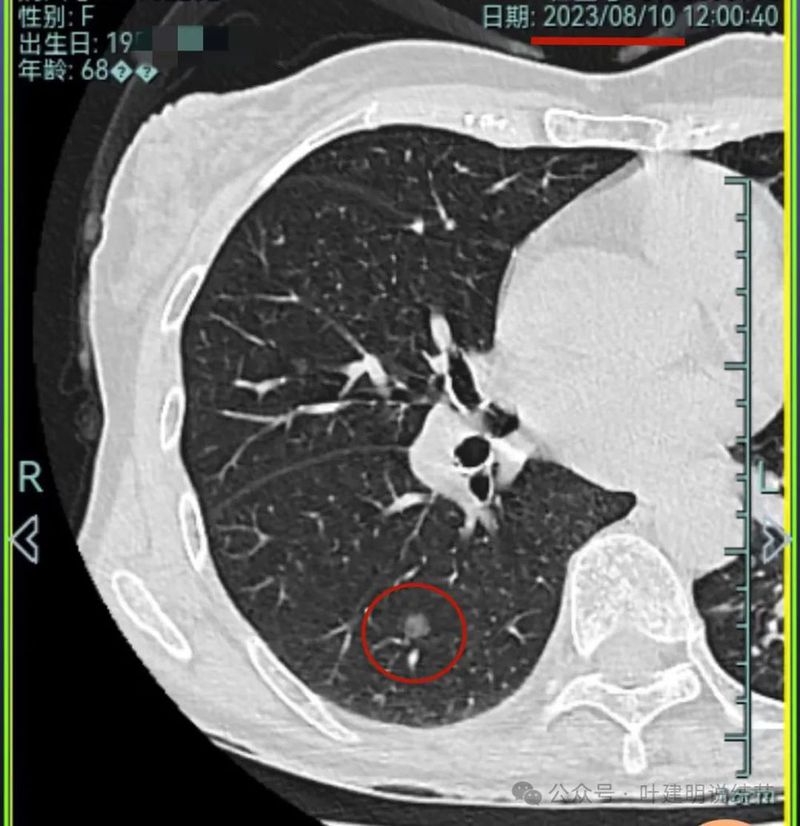

再看2023年8月的影像:

病灶1没什么进展。

病灶2与前相仿。

病灶3仍混合密度,说不上显著进展。

病灶4 仍是钙化的,大小也没有进展。

病灶5较前密度又有增高,贴着叶间裂,整体轮廓显得较之前清楚些,更符合恶性表现了,而且应该是浸润性腺癌。

病灶6与前相仿。